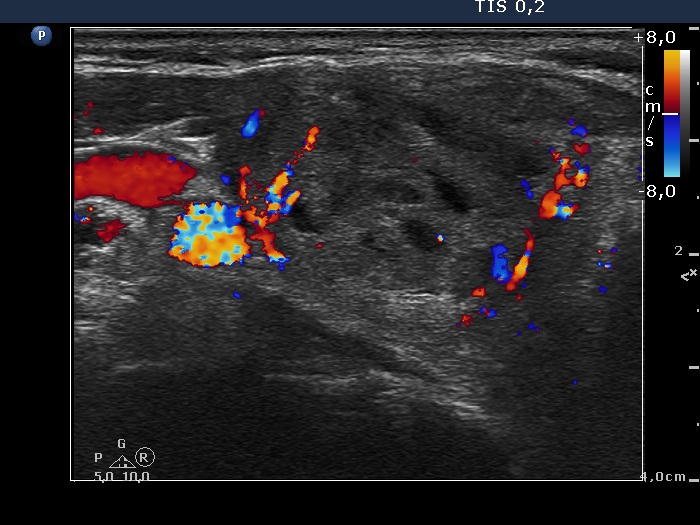

Study on 100 consecutive patients with thyroid nodule - case 006 (ultrasonographic picture 5)

Right lobe, transverse view, color Doppler mode. The nodule presents a combined perinodular and intranodular blood flow.